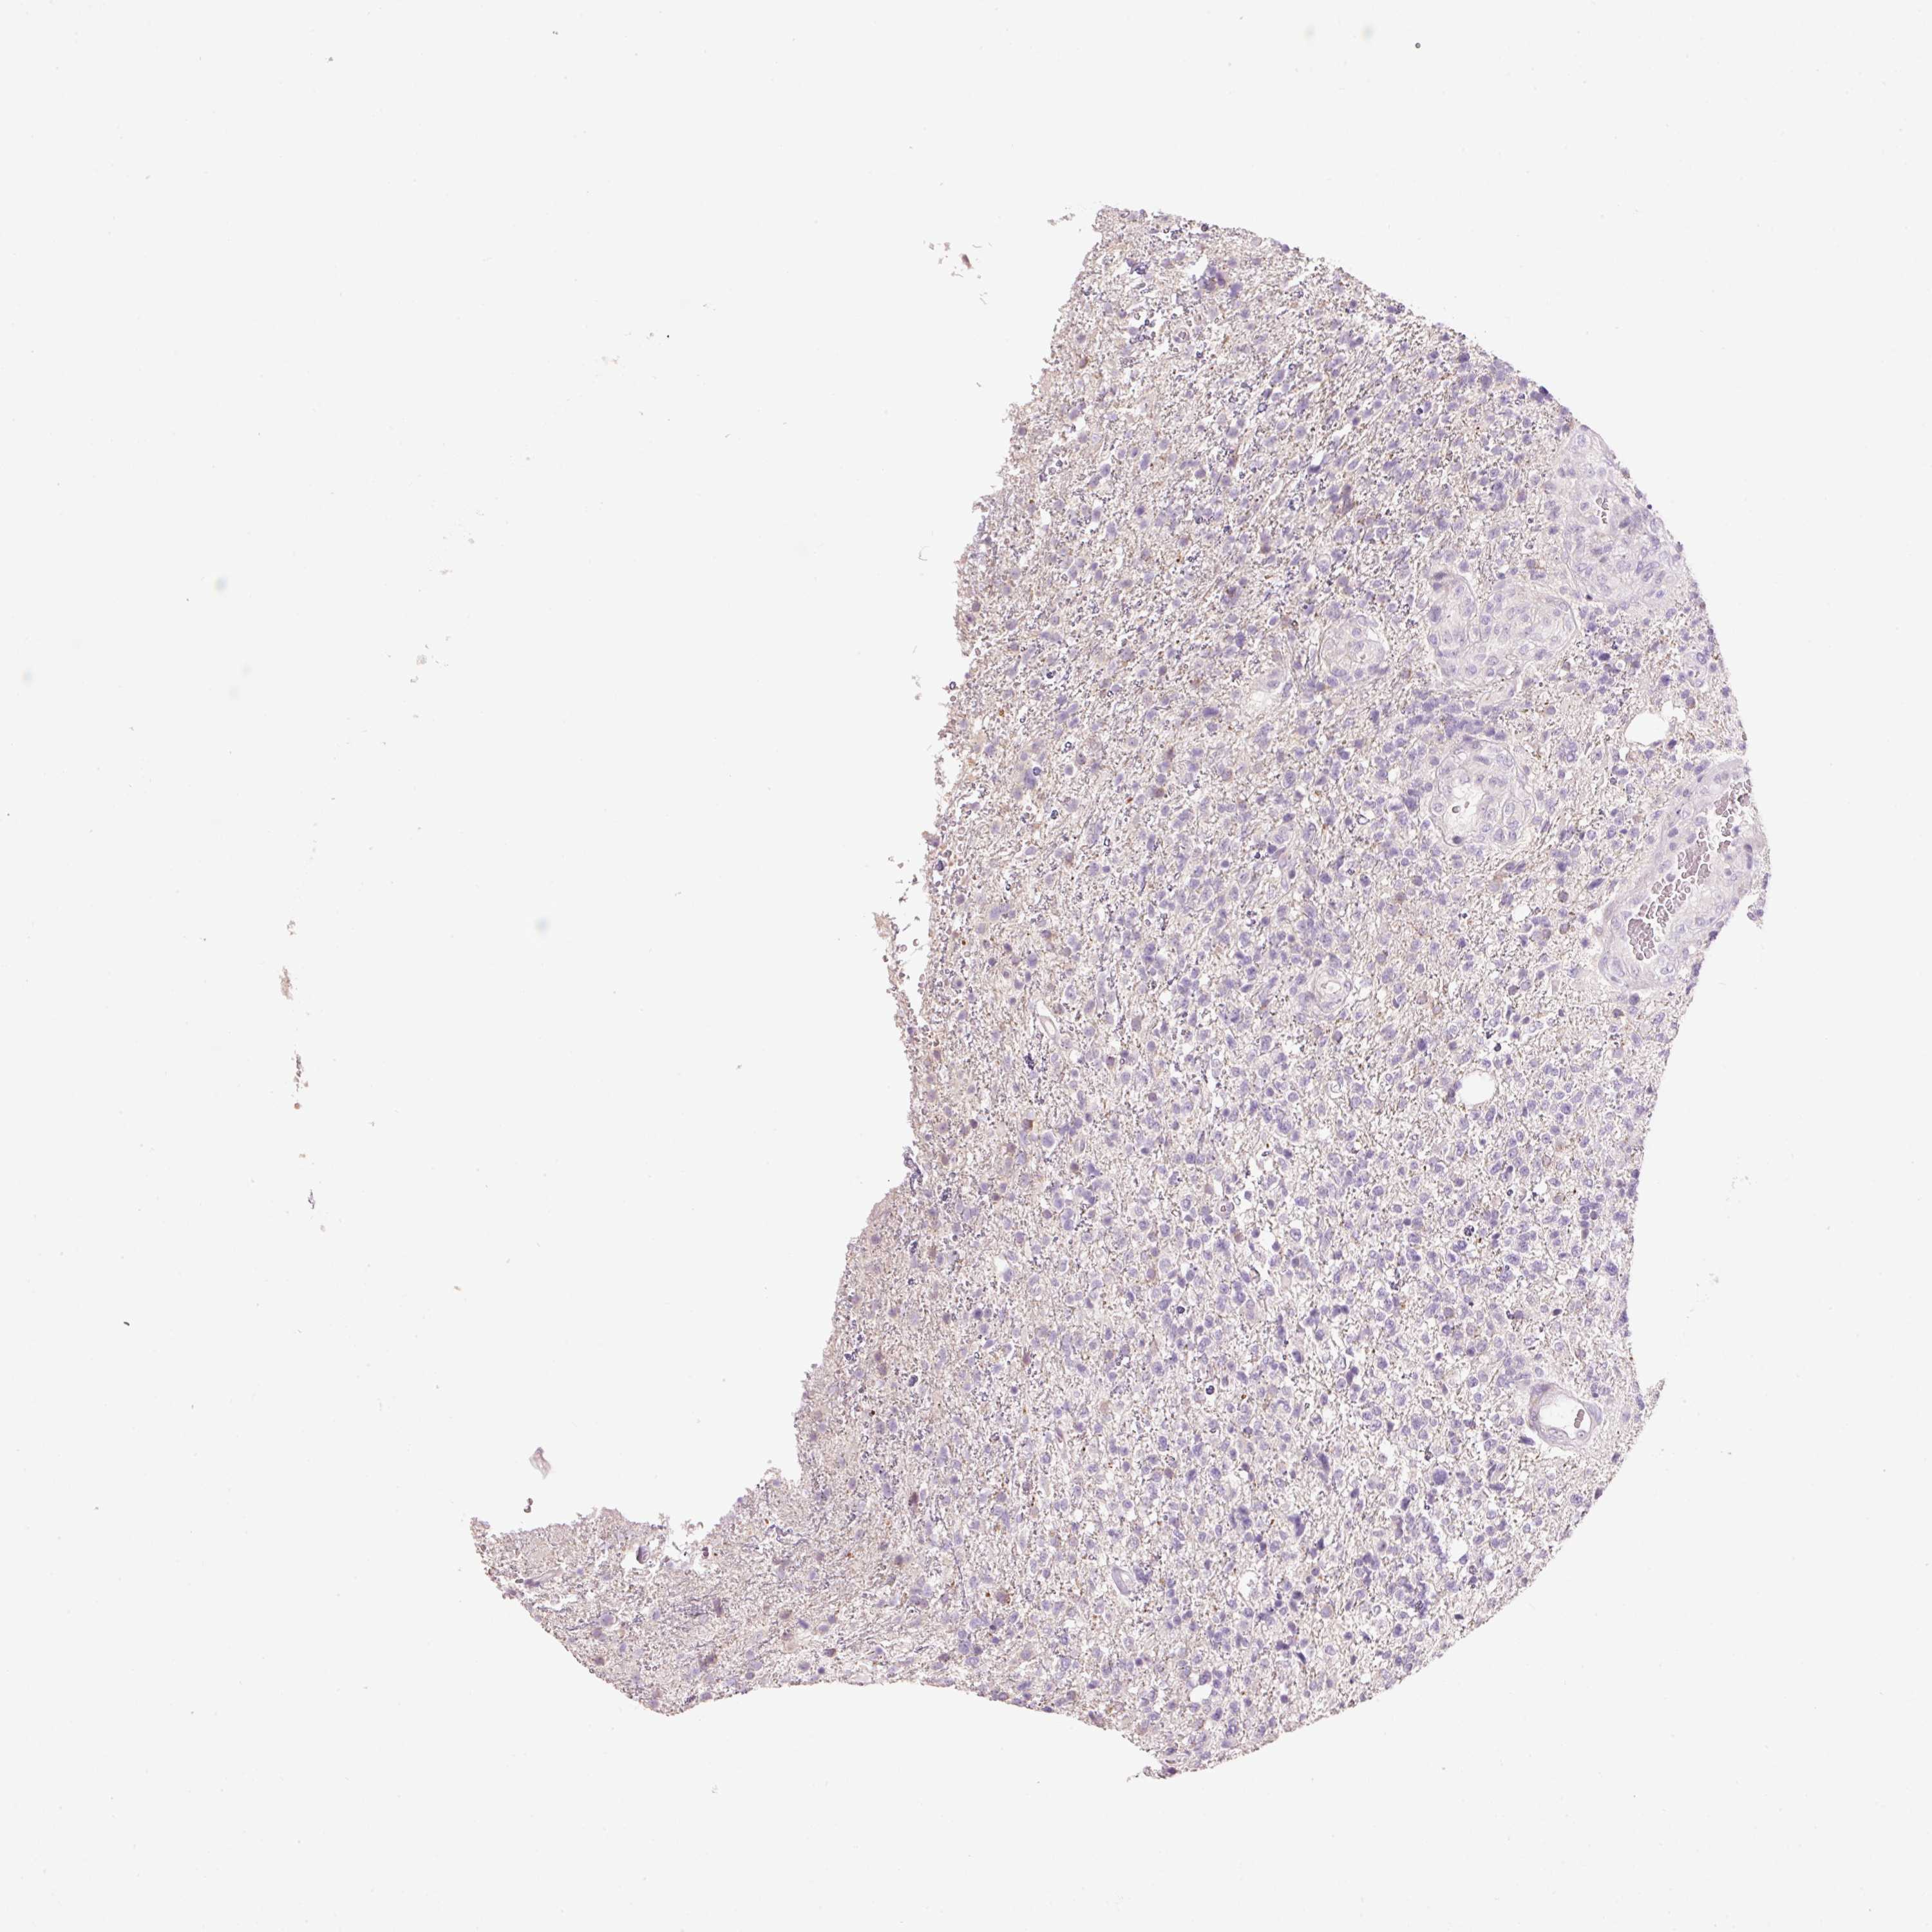

GLIOMA - Protein expressioni

A mouse-over function shows sample information and annotation data. Click on an image to view it in a full screen mode. Samples can be filtered based on level of antibody staining by selecting one or several of the following categories: high, medium, low and not detected. The assay and annotation is described here.

Note that samples used for immunohistochemistry by the Human Protein Atlas do not correspond to samples in the TCGA dataset.

Antibody stainingi

Antibody staining in the annotated cell types in the current human tissue is reported as not detected, low, medium, or high, based on conventional immunohistochemistry profiling in selected tissues. This score is based on the combination of the staining intensity and fraction of stained cells.

Each image is clickable and will lead to virtual microscopy that enables deeper exploration of all samples and also displays staining intensity scores, fraction scores and subcellular localization as well as patient and tissue information for each sample.

Antibody HPA055141

Staining

High

Medium

Low

Not detected

Intensity

Strong

Moderate

Weak

Negative

Quantity

>75%

75%-25%

<25%

None

Location

Nuclear

Cytoplasmic/membranous

Cytoplasmic/membranous,nuclear

Glioma, malignant, High grade

Glioma, malignant, Low grade